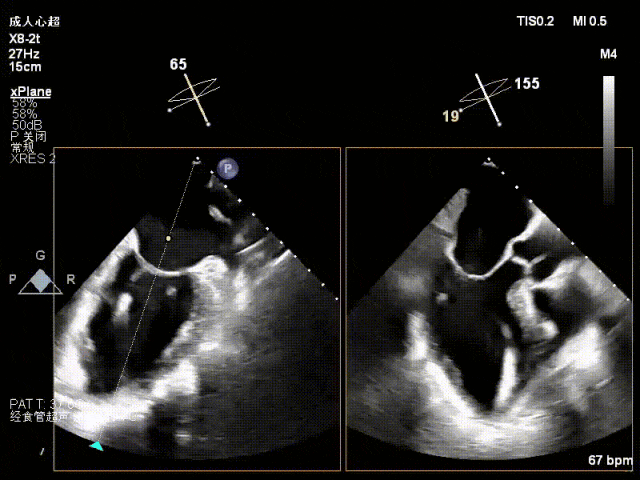

术前心超

退行性二尖瓣反流(DMR),P1/P2交界脱垂连枷(脱垂范围7mm,连枷间距4mm)

新分型:AAA型,MR 4+,VC:4×7mm

A1.5:20mm,P1.5:10mm,AP:30mm,MVA约3.8cm²

术中超声要点